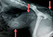

Mehrfachfrakturen nach Autounfall mit Lähmung der Hinterextremitäten, Hund